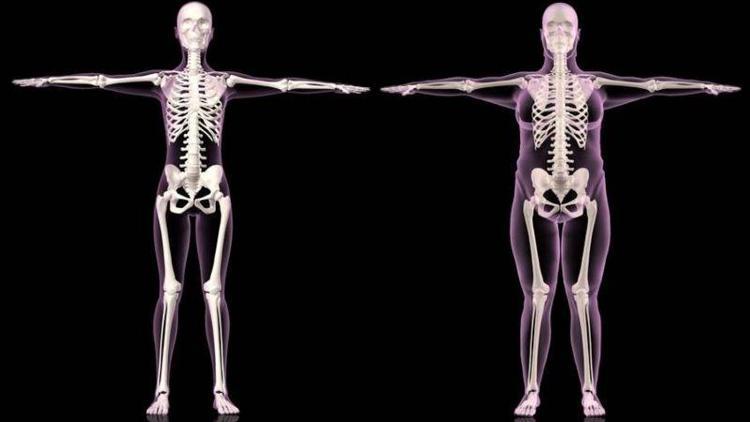

Yeme bozukluğu olarak karşımıza çıkan ve sonucunda obeziteye neden olan 'oburluğun' bir nedeni de genetik yapımız. Vücutta yer alan birçok genin yeme alışkanlıklarımızı belirlemekte önemli roller oynuyor.

Türkiye'de obez kişi sayısını günden güne arttığına dikkat çeken Öğretim Üyesi Dr. Öğr. Üys. Akın Sevinç, bireylerde görülen obezitenin altında yatan metobolik nedenlerin yanı sıra genetik faktörlerin önemine dikkat çekiyor. Bu genlerin insanlardaki dağılımı kişilerin obeziteye yatkınlığını belirliyor.

Vücutta bulunan 8 gen insanların davranışlarını etkiliyor. Bu genler son yıllarda oluşmadı. Davranışlarımızı yönetmeleriyle bizim yeme alışkanlıklarımızı enerji metabolizmamızı belirliyorlar. Genlerimiz milyonlarca yıllık evrim sürecinde hassas işlemler sonucunda oluşuyorlar. Yani genlerimiz aslında milyonlarca yıl önce kodlanmaya başladı. Genetik yapımız bu kodlanma esnasında birçok aşamadan geçti. Ancak bu kodlamalardan bazılarının hızla değişen ve globalleşen dünyanın gündelik koşullarına uyum sağlayamadığı için bu uyumsuzluk bizlerde obezitenin de dahil olduğu birçok rahatsızlık olarak olarak ortaya çıkıyor. Örneğin, evrimsel olarak enerji dengemizi korumakla görevli bir gen, ki bu gen büyük bir ihtimalle buzul çağlarında türümüzün devam etmesini sağlamıştı, ama günümüze geldiğimizde maalesef bir restorana gittiğimizde tek ya da buçuk porsiyon ile gözümüzün doymasına neden oluyor. Bu genler, bu ve bunun gibi birçok mekanizmayı tetikleyerek bizim yeme alışkanlıklarımızı belirlemede çok büyük rol sahibi ve artık genetik testler bu genetik faktörleri belirlemede çok büyük yol kat ettiler.